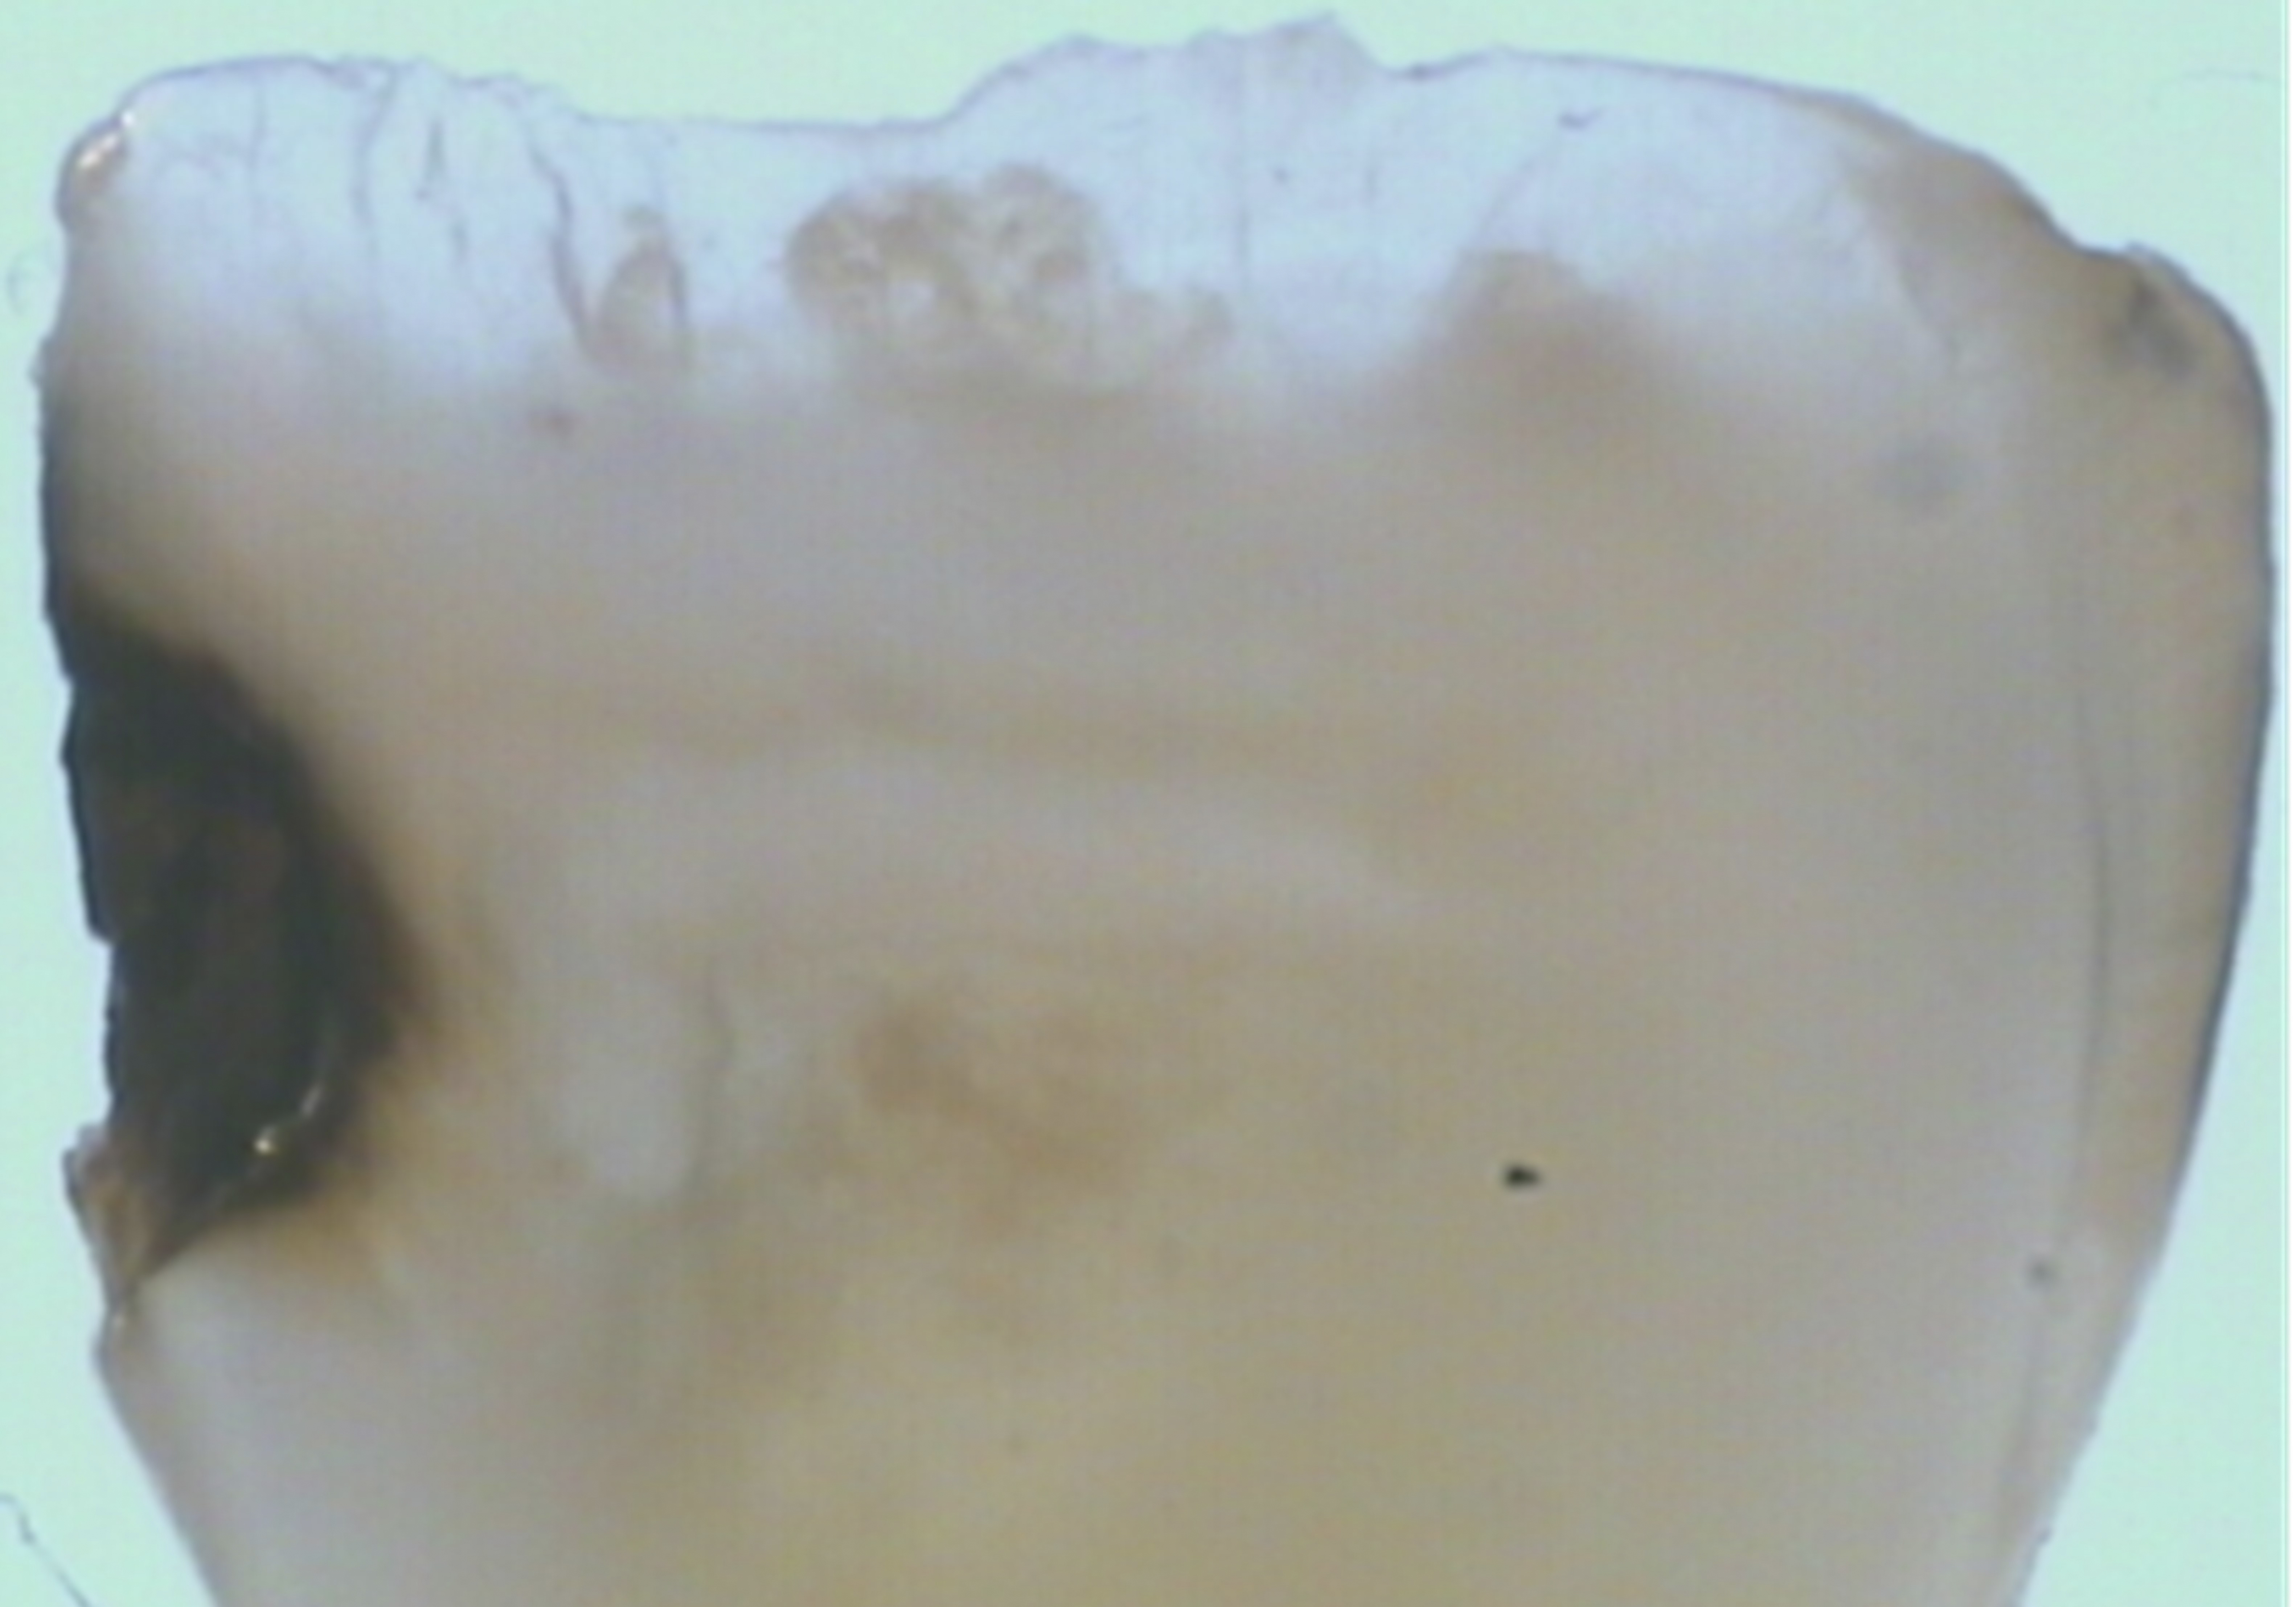

There are several advantages of using SDF in dental treatment. First, it showed an antimicrobial activity against mono-species, dual-species, and multi-species cariogenic biofilm.14-16 Silver ions are bactericidal metal cations that inhibit biofilm formation.17 Studies have indicated that silver interacts with sulfhydryl groups of proteins and DNA, thus altering hydrogen bonding and inhibiting respiratory processes, DNA unwinding, cell-wall synthesis, and cell division.18 At the macro level, these interactions affect bacterial killing and inhibit biofilm formation.17 Second, fluoride promotes caries lesion remineralization. Fluoride has been indicated to react with hydroxyapatite and generate calcium fluoride, which is a reservoir of fluoride, and facilitate further remineralization.19 An ex vivo study reported surface microhardness of the surface layer of the arrested caries after SDF applications was comparable with the unaffected sound dentin20 (Figure 1 and Figure 2). This is consistent with another study, in which a high remineralized zone was observed on the surface of arrested caries from exfoliated teeth with SDF treatment21 (Figure 3 and Figure 4). Third, its application procedures are simple and do not require injection or drilling, and the treatment does not involve expensive support infrastructure equipment such as piped water and electricity. The simplicity of the treatment is conducive to treating caries in apprehensive young children who may have intense dental fear, uncooperative patients with special needs, or elderly patients who have difficulty adapting to traditional dental care. It also allows trained workers to deliver the treatment to people who live in the area but who may not be able to easily access dental service.22 Patient compliance and satisfaction is often good when the patient is provided a clear explanation of the treatment outcome.23,24 Finally, the cost of SDF treatment is low and should be affordable in most communities.

Fig 1. Ground section of a primary incisor with arrested caries lesion after SDF treatment. Fig 1: Arrested caries that had SDF treatment. Fig 2: Microhardness of dentin (in median Knoop hardness number) in soft and SDF-arrested caries according to the distance from the lesion surface. (images from Chu and Lo, 200820 [reprinted with approval])

Fig 1 and Fig 2. Ground section of a primary incisor with arrested caries lesion after SDF treatment. Fig 1: Arrested caries that had SDF treatment. Fig 2: Microhardness of dentin (in median Knoop hardness number) in soft and SDF-arrested caries according to the distance from the lesion surface. (images from Chu and Lo, 200820 [reprinted with approval])